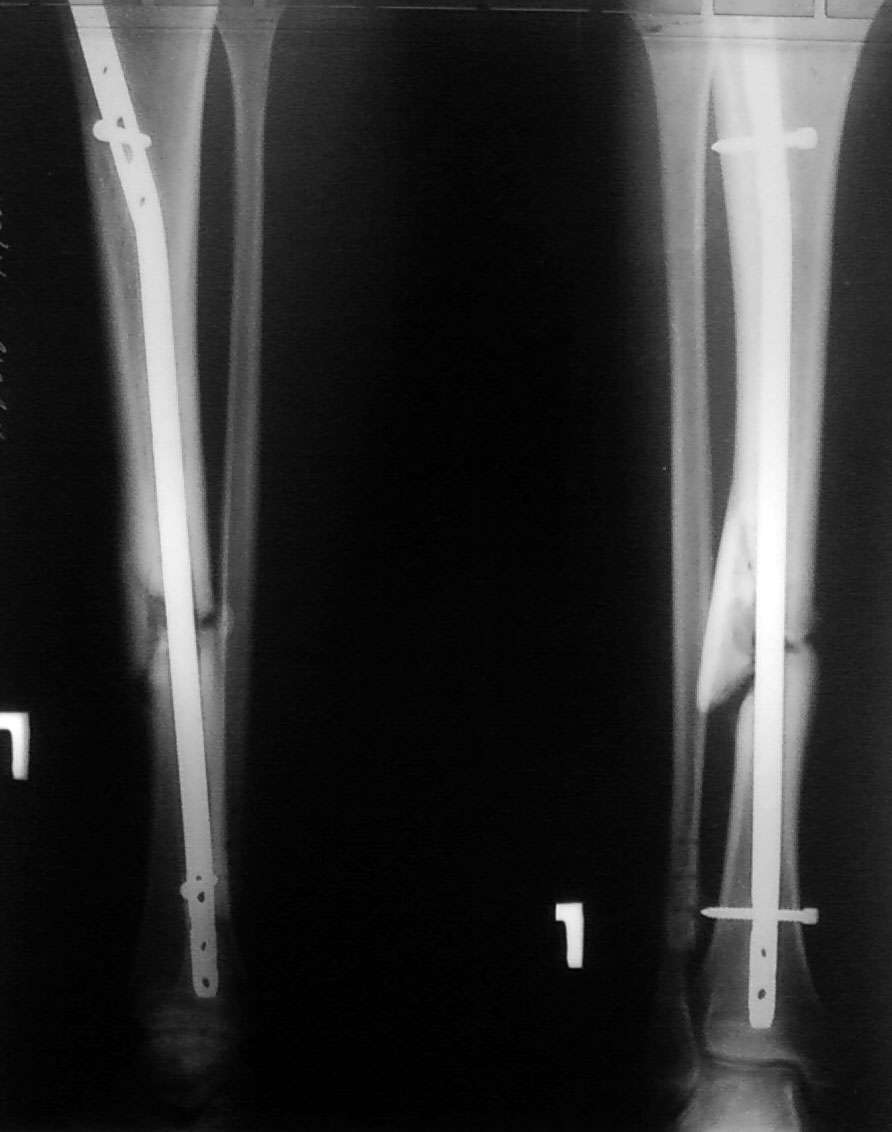

Несросшийся перелом через 9 месяцев после БИОС голени

Пациент 24лет травма в мае 2009г, сбит а/м. диагноз: вторично-открытый перелом правой м/б

кости в н/3, оскольчатый перелом б/б кости справа. Рана по наружной поверхности 2*1 см. В

первые сутки выполненно ПХО открытого перелома м/б кости остеосинтез 1/3трубчатой

пластины (синтез выполнен из-за того, что проксимальный отломок мог вызвать угрозу

внутреннего пролежня) и БИОС б/б кости стерженем Chm в статическом варианте. П/о период без

осложнений. Через 2 месяца выполнена динамизация. Ходил без дополнительной опоры. Через

6месяцев обратился с жалобами на боль в н/3 голени. На контрольном снимке сломана пластина

1/3 трубки, вполнена операция - удаление пластины. Обратился сегодня с жалобами на боли в

области концов стержня (в/3 и н/3), боль при ходьбе. Что делать? Мы думаем заменить стержень

на 11мм (сейчас 9мм) и рассверлить канал с целью освежить зону перелома. СПАСИБО.